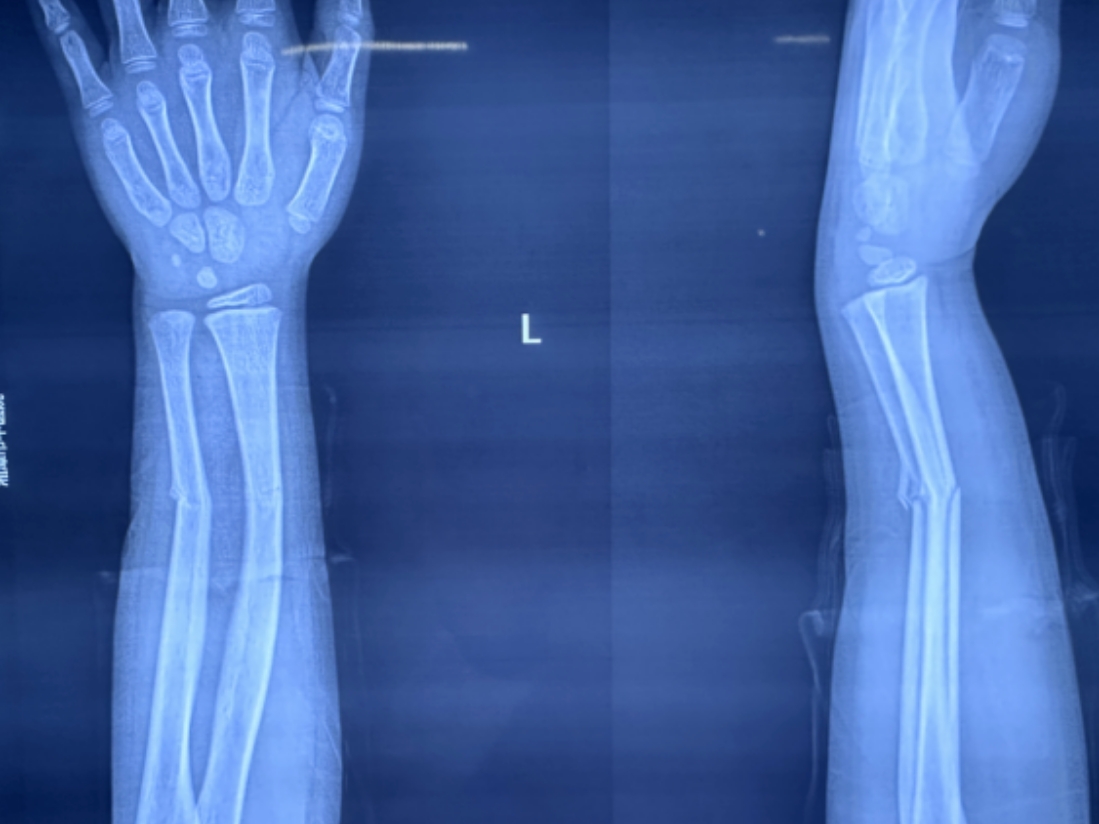

橈骨遠(yuǎn)端骨折復(fù)位前 橈骨遠(yuǎn)端骨折復(fù)位后